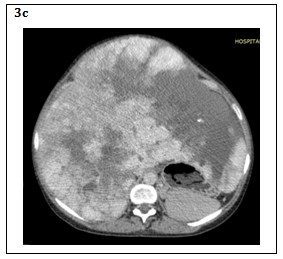

In ultrasound, HH classically appears as a homogeneous hyperechogenic focal lesion with a relatively clear limit, in addition of color with Doppler provides better qualitative and quantitative data thus increasing the sensitivity and specificity of the test.12 In recent years, it has begun to use microbubble ultrasonography where peripheral lesions show peripheral reinforcement that expand centripetally during the portal venous phase, completely filling in the delayed images. However, all these ultrasound characteristics are not usually observed in the HHG, where thrombosis, hemorrhage, fibrosis, or calcification show a heterogeneous image of the lesion12,13 (Figure 2).

Figure 2 Big heterogeneous mass occupying both hepatic lobes with zones of hemorrhage and calcification that with the addition of Doppler can be delimited relatively.

Photos from the Department of Radiology, “Hospital Regional Docente de Enfermedades Neoplásicas”